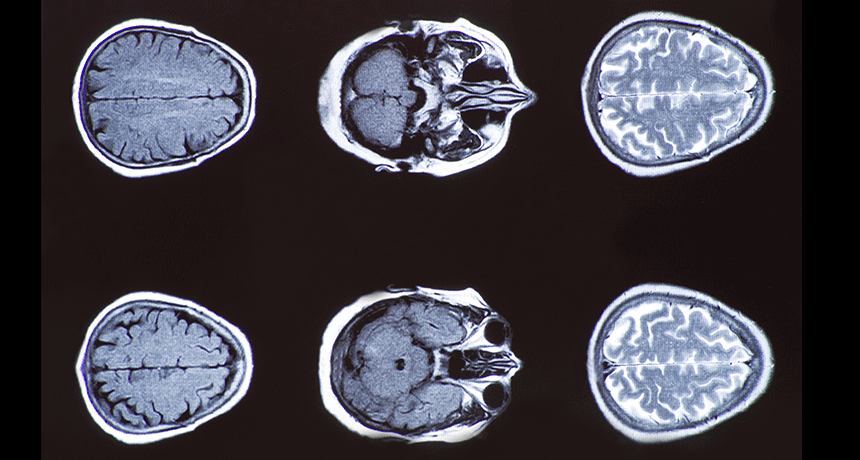

computerized axial tomography (CAT or CT, for short). A special kind of X-ray scanning technology that produces cross-sectional views of the inside of a bone or body.

computerized tomography (CT, for short). A special kind of X-ray scanning technology that produces cross-sectional views of the inside of a bone or body.

scanner A machine that runs some sort of light (which includes anything from X-rays to infrared energy) over a person or object to get a succession of images. When a computer brings these images together, they can provide a motion picture of something or can offer a three-dimensional view through the target. Such systems are often used to see inside the human body or solid objects without breaching their surface.